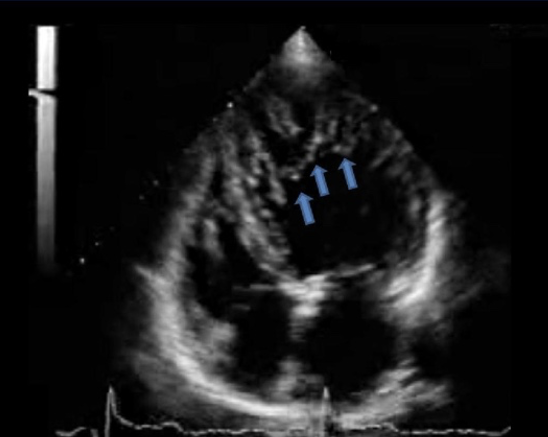

Heterogeneous speckled appearance of the myocardium of the RV and LV consistent with?

Infiltrative cardiomyopathy